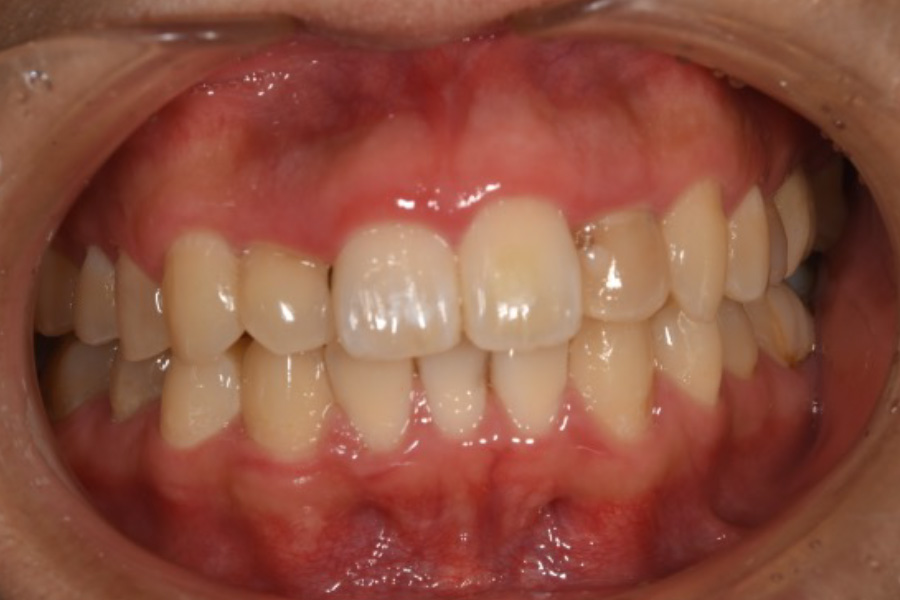

右上右下の八重歯、

下の歯のガタつき、

上の前歯の突出感が気になる

【マウスピース矯正】

- 担当医

- -

- 主訴

- 右上右下の八重歯、下の歯のガタつき、上の前歯の突出感

- 期間

- 2年

- 費用

- マウスピース矯正

1,024,000円(税込)

- 治療内容

- 目立ちにくいマウスピース矯正(非抜歯矯正)

歯と歯の間に隙間をつくることにより、歯列弓を広げながら治療を行いました。

- 治療に伴うリスク

- ・後戻りする可能性があるのでリテーナーを最低でも矯正期間以上はつけること

・稀にほっぺた、唇、舌などに口内炎や傷ができることがあります